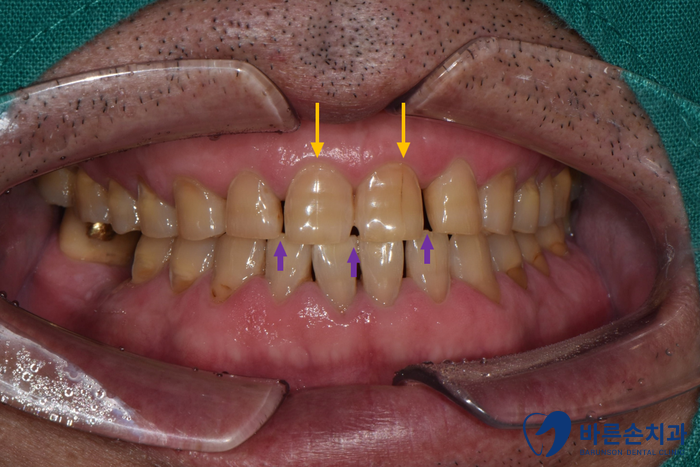

50대 중후반 남성 환자분께서 내원하셨습니다.

앞니에 금이 가 있는게 보기가 싫고, 치아 사이 공간도 보기싫다고 하셨어요

Before 25.09.13

노란 화살표 가 가르키는 곳을 보면

치아 표면에 균열이 생긴 것을 볼 수 있습니다.

생긴 균열을 따라서 변색이 같이 진행되고 있어요

보라색 화살표가 가르키는 곳은

치아가 벌어져 있어요.

기능적으로 전혀 문제가 없지만

심미적이지 않은 부분입니다.

보기 싫은 두 문제를 해결 하기 위해

지르코니아 크라운 치료를 하기로 합니다.